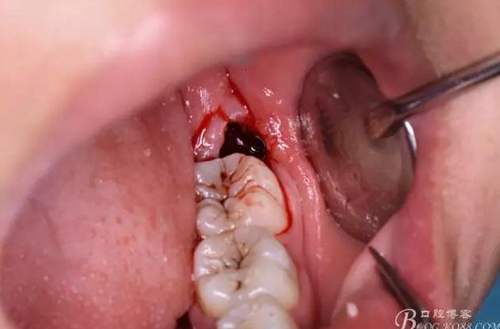

圖14.38牙根即將脫出牙槽窩

圖15.牙根脫位受阻,遂將牙根分為兩根

圖16.取出38遠(yuǎn)中根

圖17.然后取出38近中根